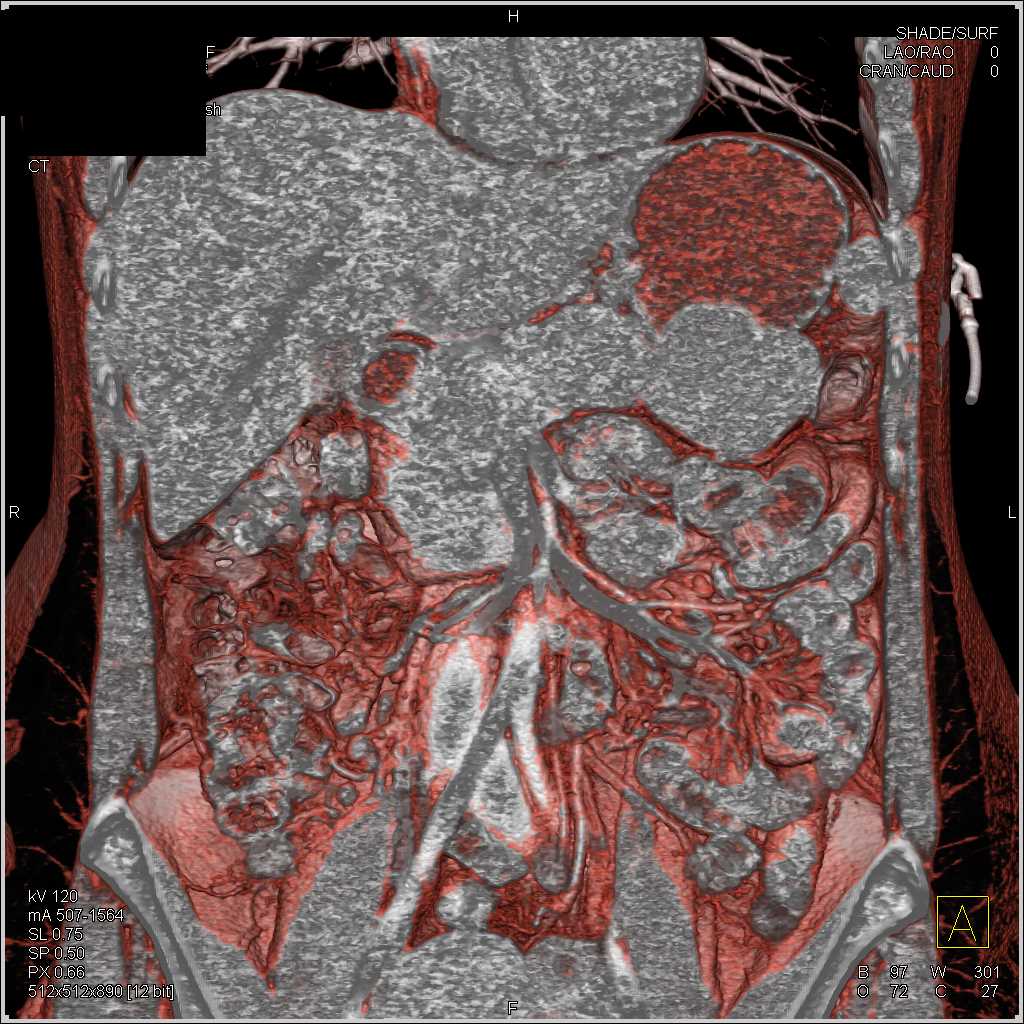

Mass Pushes on Tail of Pancreas was Ganglioneuroma